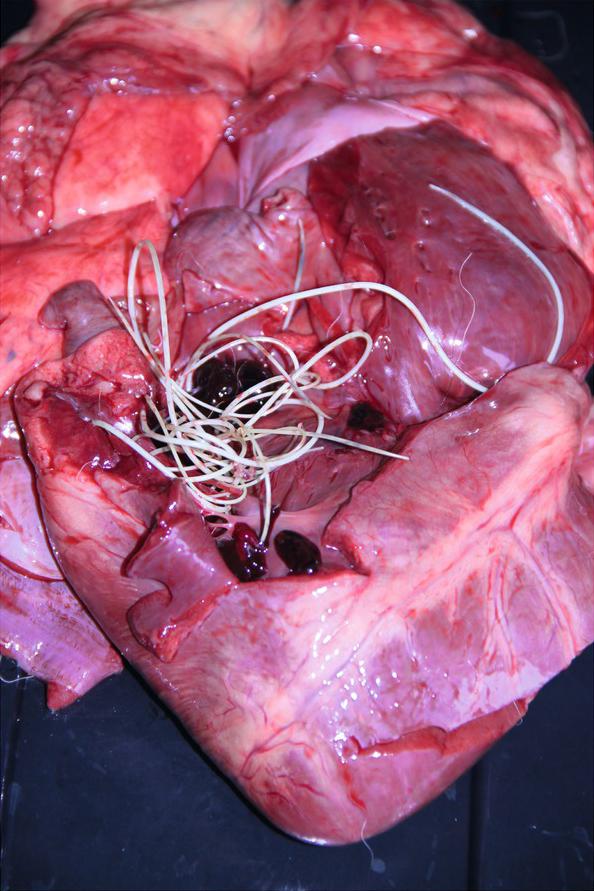

The cardiologic examination was planned, however, the condition deteriorated and dyspnoea appeared. The X-ray revealed an alveolar pattern in the cranial lung lobes and the heart silhouette was not visible due to changes in the lungs. The dog died after 5 days and no other examinations could be performed. The dog was submitted for post-mortem examination and adult D. immitis worms were found in the right heart ventricle, and several specimens were identified in the pulmonary arteries (Fig. 1). In addition, pulmonary oedema was discovered and the right ventricle was dilated. The necropsy findings included: chronic interstitial nephritis and chronic cystitis, acute catarrhal jejunitis, sediment in the gallbladder and icterus. Cardiovascular and respiratory failure in connection with kidney damage was assigned as an immediate cause of the death.

Fig. 1

Adult Dirofilaria immitis worms in the right heart ventricle of Tibetan Mastiff male dog.